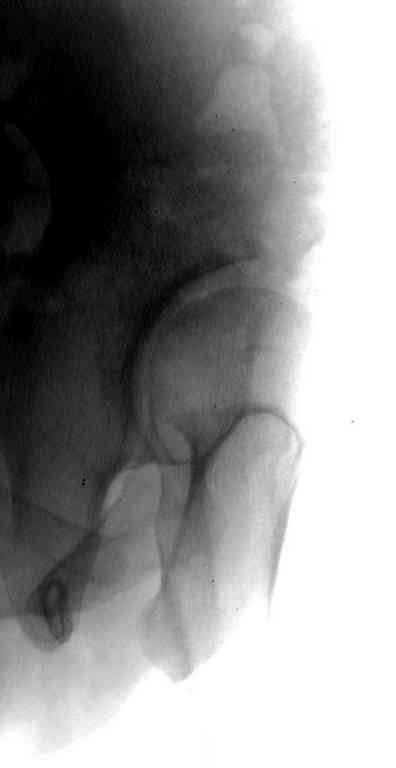

Типичная концовка проигнорированного диспластического состояния сустава. Дисплазия тазобедренного сустава часто встречающаяся патология у жителей Центральной Азии вследствие тугого пеленания в детстве. Традиционно ребенок находится в течение дня в так называемой кроватке "бешик", удобной в быту, но она впоследствии приводит к недоразвитию тазобедренного сустава.

Это первые признаки начала деструкции сустава, и возможно, аналгетики помогут для купирования болей, но в течение очень короткого времени от сустава ничего не останется, и в дальнейшем останется только артропластика.

Данный сустав в начальной стадии разрушения, но все-таки я бы сделал обзорный таз и отдельные снимки сустава в 30 градусной абдукции и аддукции. Также снимки с внутренней и наружной ротацией для оценки состояния головки бедра.